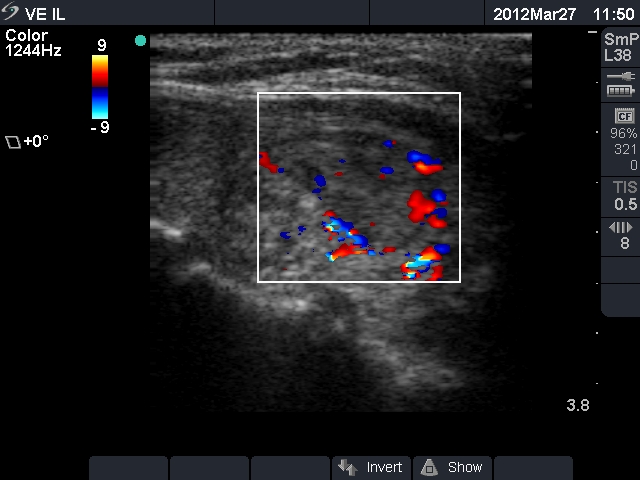

Right lobe, longitudinal scan

Other section of the left lobe, longitudinal scan, color Doppler mode. Both peri- and intranodular blood flow can be seen.